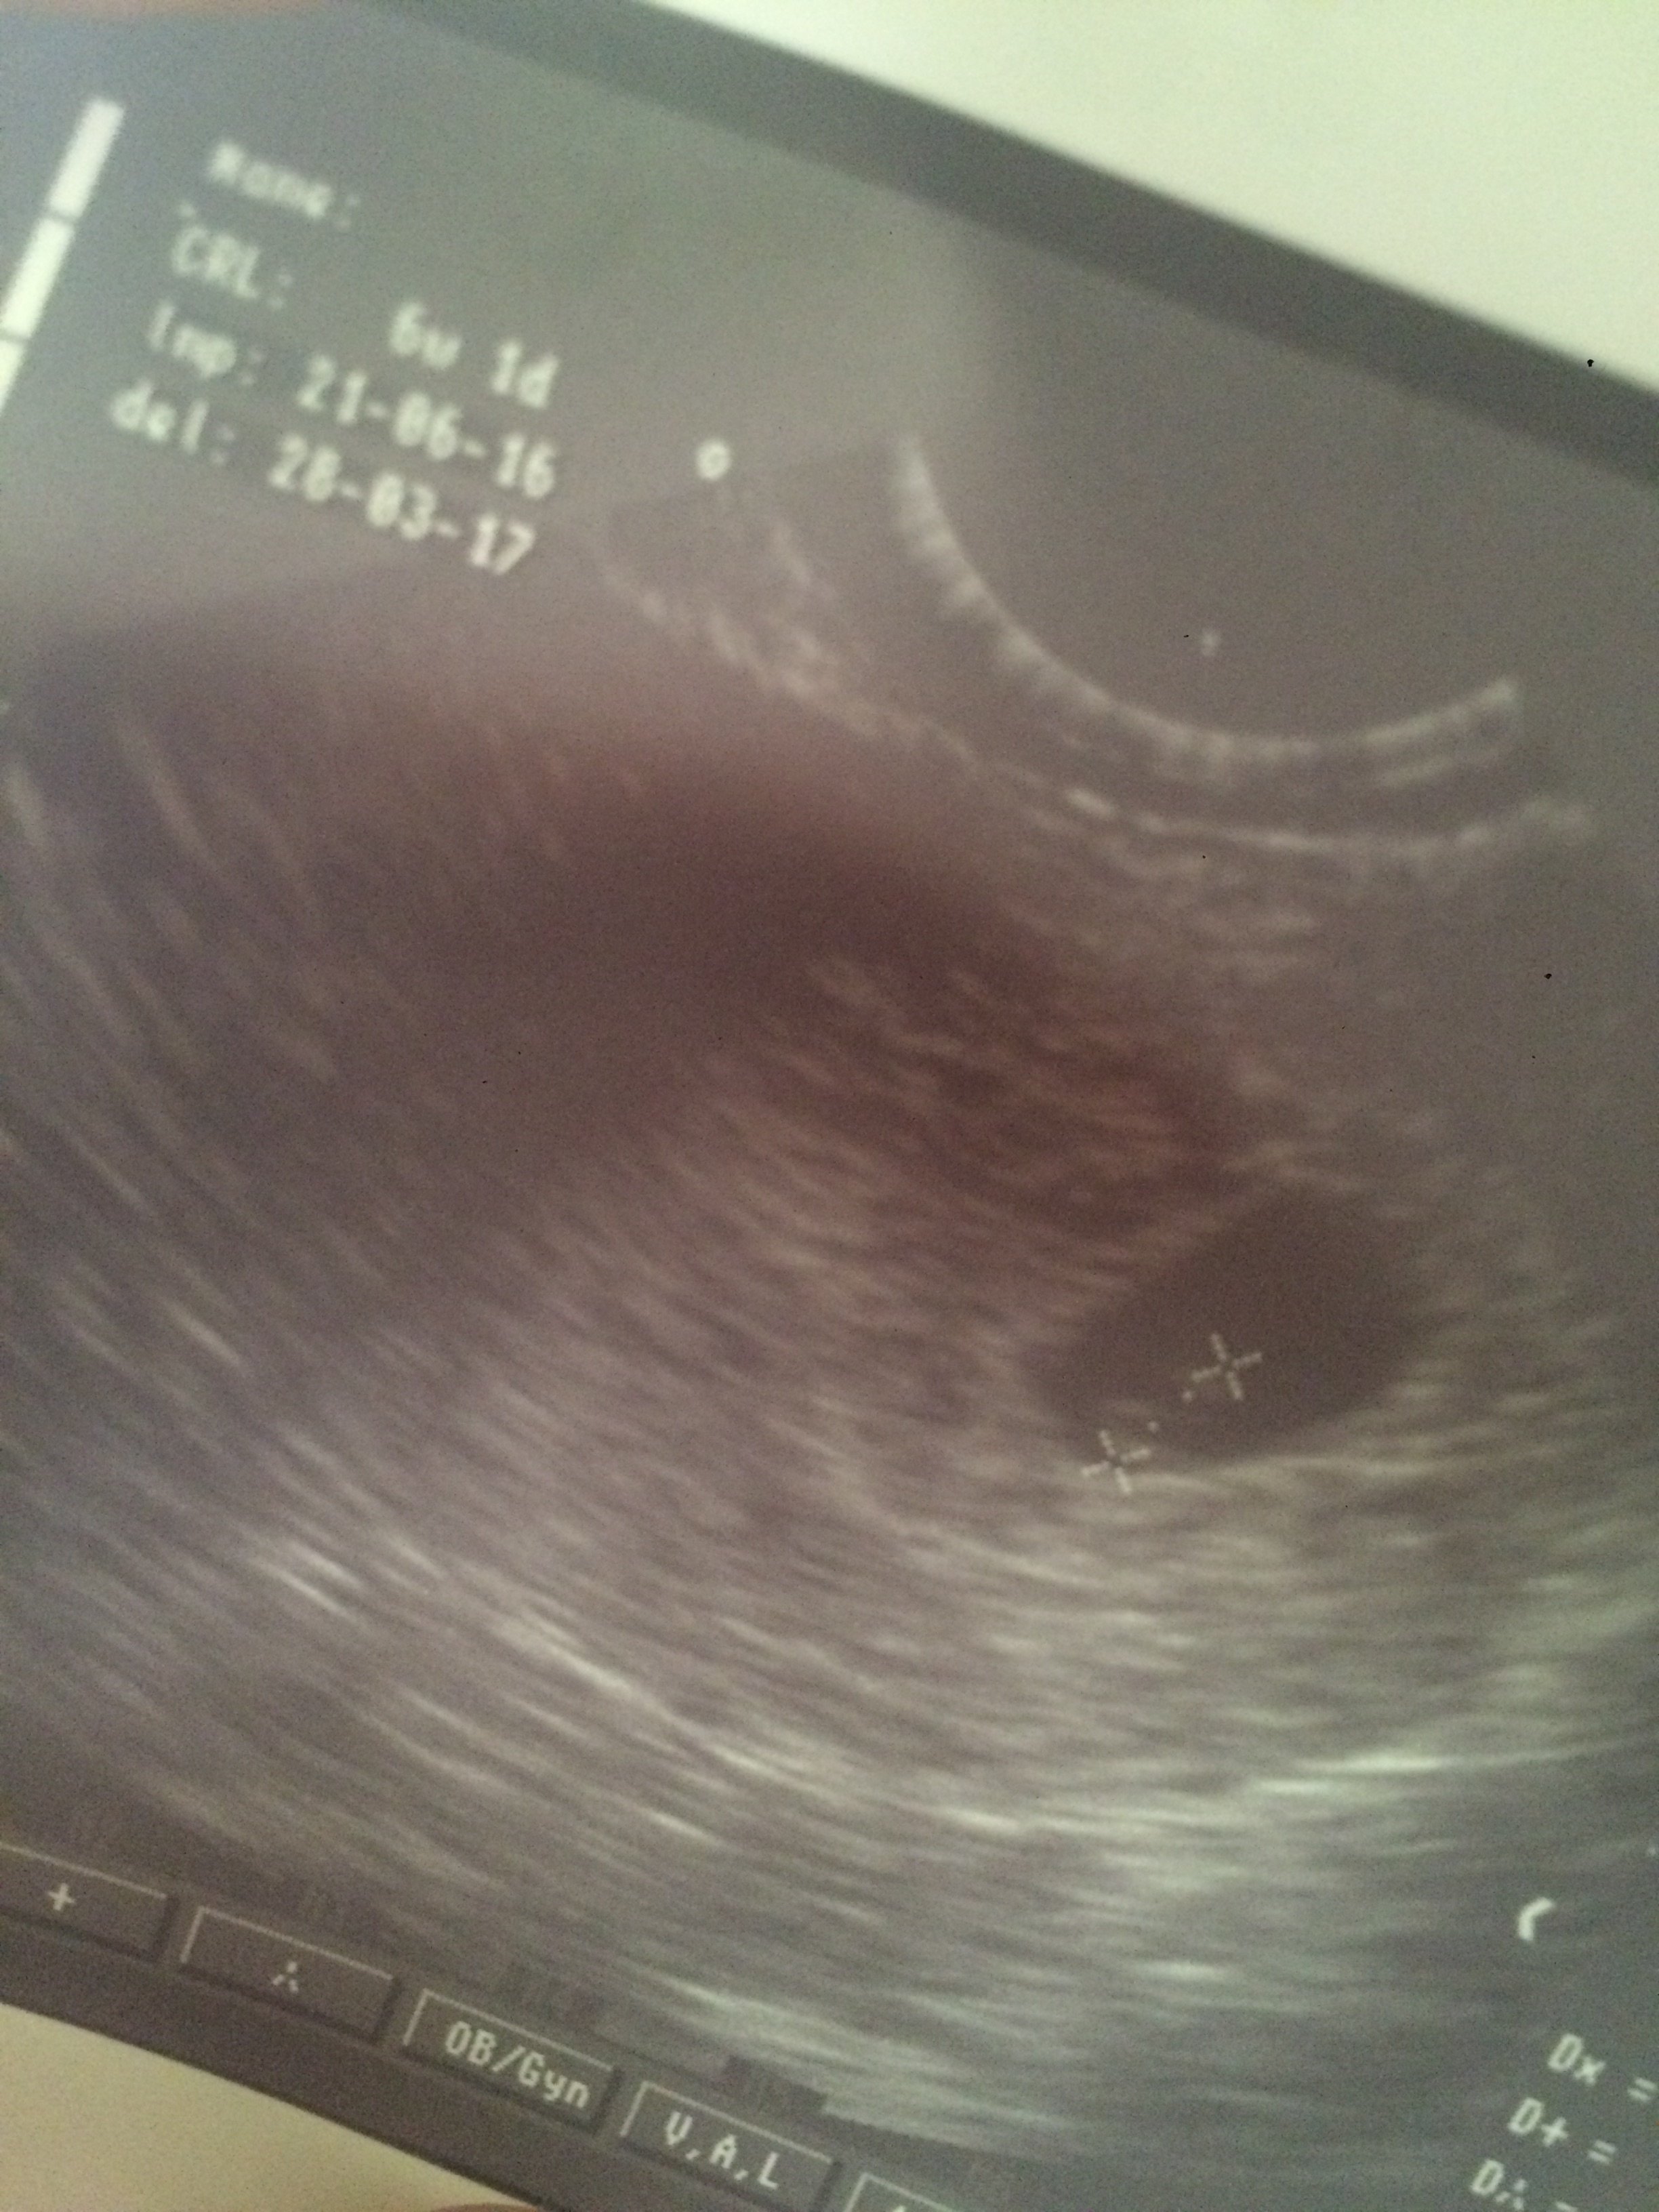

Mam zdjęcie sprzed tygodnia, widać tam płód. Moze na zdjęciu wyglada jak kreseczka, ale jak lekarka mi pokazywała na monitorze to wyglądał jak taka malutka fasolka :( niestety na samym zdjęciu zdjęcia tego nie wdiac tak bardzo jak na żywo. A jestem z Krakowa, wybieram sie teraz do porani na 2 pułku lotniczego

1512 trzymam za ciebie mocno kciuki u mnie pierwsze usg wyglądało tak samo jak u ciebie było widać zarodek. Daj znac koniecznie jak tam.

A to mój maluch: